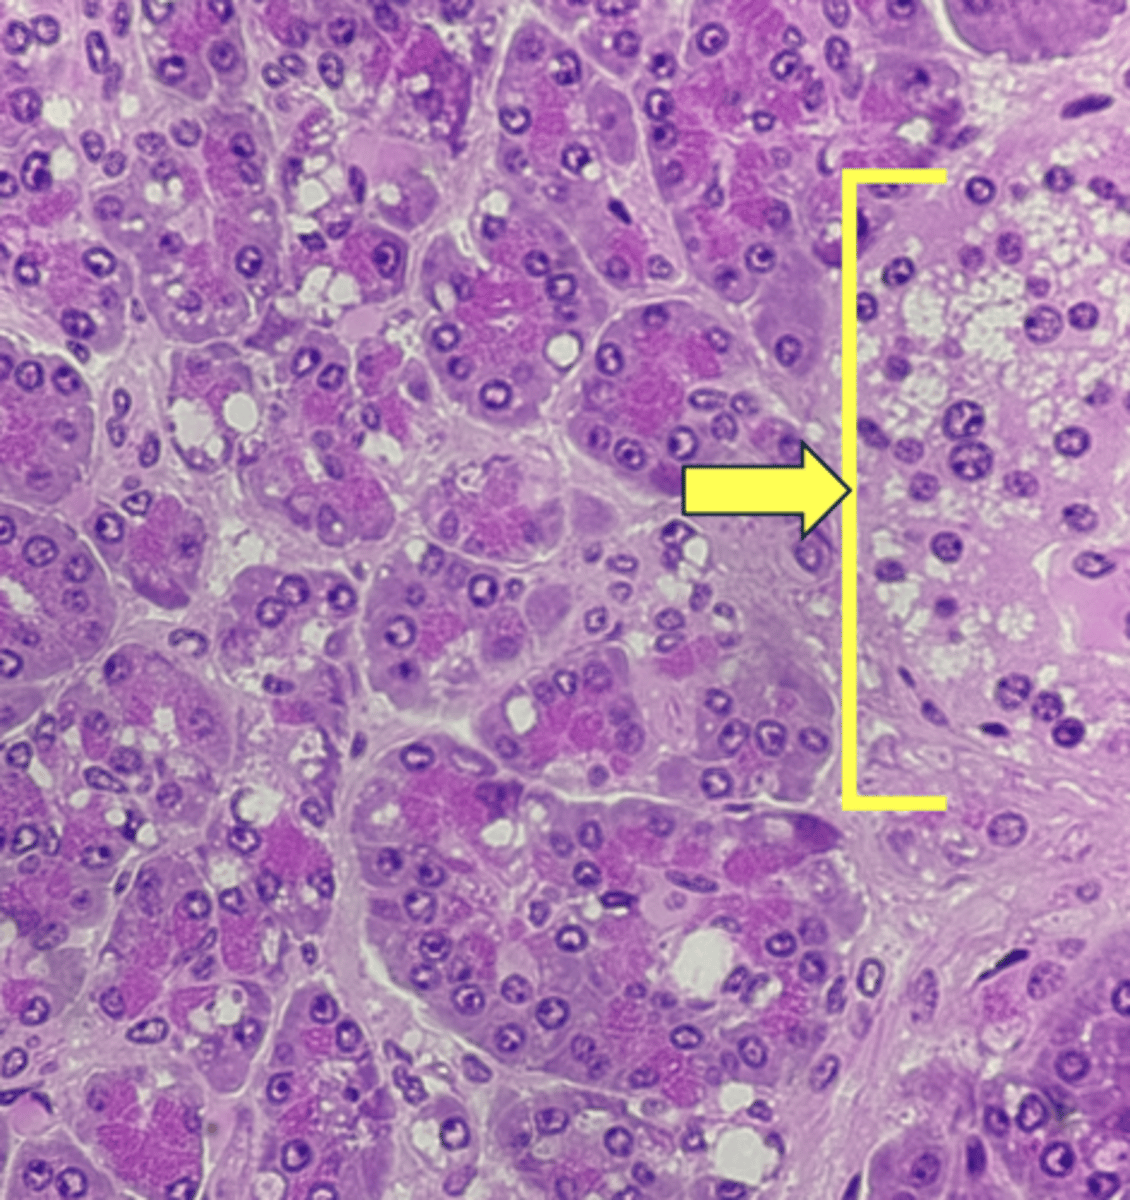

Pancreas

name the tissue

pancreatic islets

Acinar cells- digestive enzymes, amylase, lipase, & proteases

(pancreas)

type of cell & what it secretes?